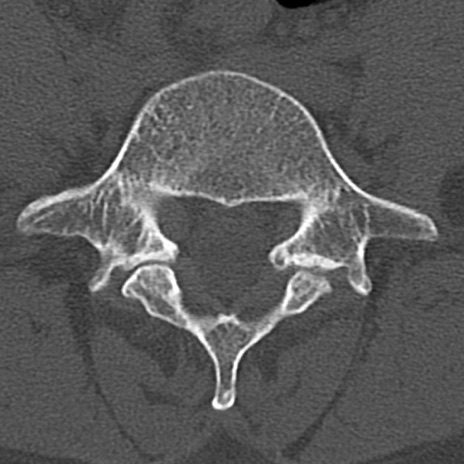

【整形】TIPS症例4 腰椎CT(横断像)

腰椎CT

横断像と矢状断像